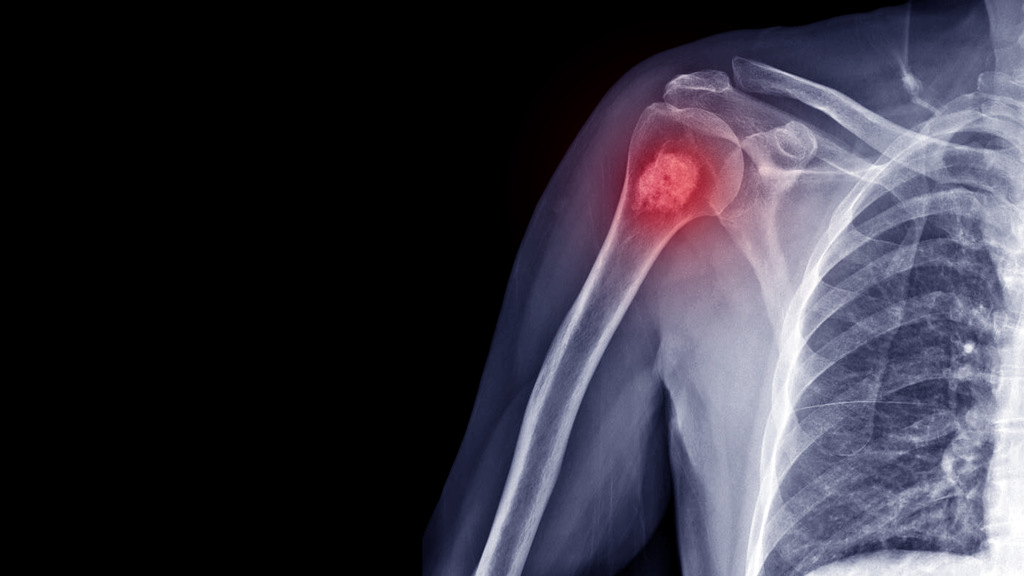

Osteoporose pode virar câncer?

A resposta é: não, porém precisamos entender um pouco mais o porquê as pessoas tendem a fazer tal confusão.

Câncer e osteoporose são doenças diferentes, que têm causas e mecanismos distintos.

A osteoporose é uma doença óssea, que envolve a perda de densidade e resistência dos ossos, enquanto o câncer é uma condição que envolve o crescimento anormal e descontrolado de células no corpo, que podem invadir e destruir outros tecidos e órgãos.

No entanto, existe uma relação entre a osteoporose e o câncer, que pode ser explicada por dois aspectos: o risco de fraturas e o uso de medicamentos.

Pessoas com osteoporose têm maior risco de câncer ósseo?

Isso é parcialmente verdade, já que embora a osteoporose em si não cause câncer ósseo, a fragilidade dos ossos associada à doença pode aumentar o risco de fraturas patológicas.

Essas são fraturas que ocorrem em um osso enfraquecido por uma doença ou um medicamento, sem um trauma significativo.

Em alguns casos raros, podem revelar a presença de um câncer que se originou em outra parte do corpo e se espalhou para os ossos, causando metástases ósseas.

As metástases ósseas são mais comuns em cânceres de mama, próstata, pulmão, rim e tireóide.